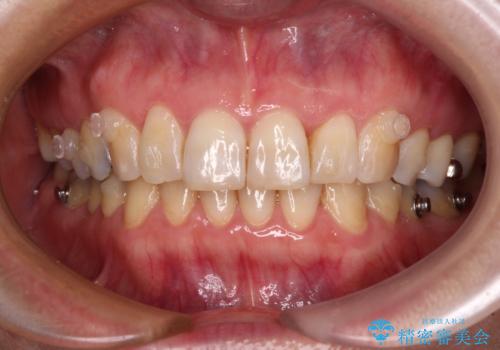

インビザラインは、ワイヤー矯正と異なり、患者様がしっかりと使うということが治療成功の絶対必須条件となります。

十分な装着時間が達成できず、治療途中で後戻りを起こすことがあり、インビザラインの有効期限内に終了させることができませんでした。

ワイヤー矯正や別システムのマウスピース矯正を利用することで、何とか終了させることができました。